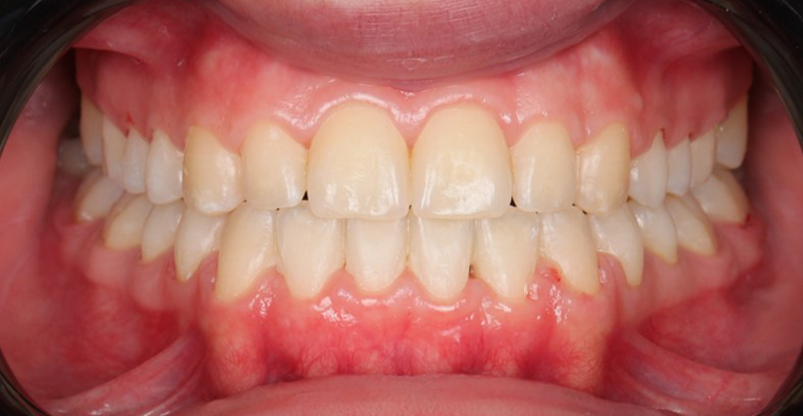

At the end of treatment, the patient’s occlusion was corrected to Class I molar and canine relationships with a physiological overjet and overbite. Irregularities in both arches were eliminated, arch forms were coordinated, and incisor torque was effectively controlled to position the roots centrally within the alveolar bone, enhancing stability. Satisfactory intercuspation was achieved in both the anterior and posterior segments, with maintenance of midline coincidence and periodontal health throughout treatment. The case was finished and transitioned into the retention phase using fixed retainers in the maxillary and mandibular anterior regions.